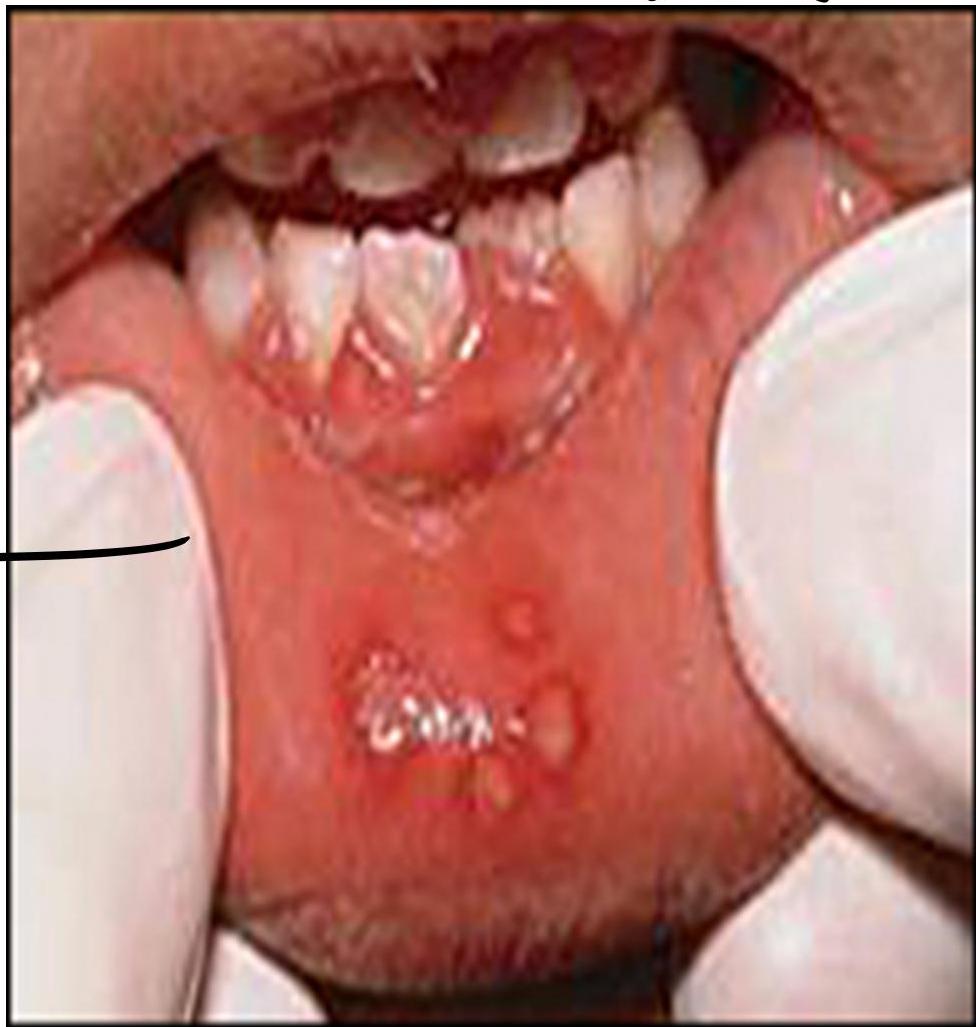

Herpetic Gingivostomatitis

3 years old child presented with fever and refusal to eat, your examination showed

- Diagnosis ?

- Herpes simplex 1 (herpetic gingivostomatitis)

Finding:

- Aphthous ulcers

- Oral mucosa ulceration

Treatment:

- Acyclovir gel

- Severe cases: IV acyclovir